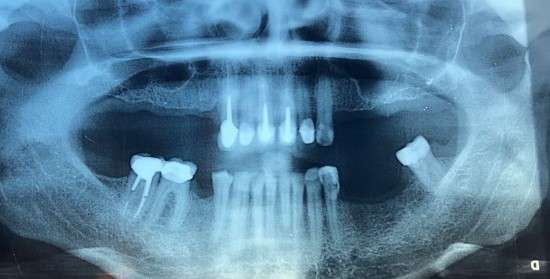

பரிஸ் 8 ஆம் வட்டாரத்தின் Saint-Lazare நிலையத்துக்கு அருகே உள்ள குறித்த Dentexia பற்சிகிச்சை நிலையத்தில் மேரி (பெயர் மாற்றப்பட்டுள்ளது) எனும் பெண் பற்சிகிச்சை மேற்கொண்டுள்ளார். வீதி விபத்தில் சிக்கிய அப்பெண் தனது மூன்று பற்களை இழக்க நேர்ந்தது. ஆனால் குறித்த சிகிச்சை மையத்தில் வாயின் மேற்பகுதியில் உள்ள அனைத்து பற்களை பிடுங்கப்பட்டதாகவும், அதற்காக அவரிடம் இருந்து €9,000 யூரோக்களை கட்டணமாக அறவிட்டதாகவும் தெரிவிக்கப்படுகிறது.

அதேவேளை, பற்களை செயற்கை முறையில் மீள பொருத்துவதற்கு கிட்டத்தட்ட இரண்டு ஆண்டுகள் எடுக்கும் எனவும், அதற்குள்ளா X-Ray, ஸ்கேன் போன்ற செயற்பாடுகளுக்காக தினமும் பணத்தை இழப்பதாகவும், மொத்த பற்களையும் பொருத்தி முடிப்பதற்கு கிட்டத்தட்ட 30,000 யூரோக்கள் வரை செலவாகும் எனவும் அவர் கவலை வெளியிட்டார்.